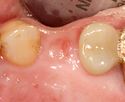

A healing abutment is attached to the implant fixture and the gingiva flap is sutured around the healing abutment.

A healing abutment is attached to the implant fixture, and the flap of gingiva is sutured around the healing abutment.

When the metal of an implant becomes visible a connective tissue graft is used to improve the mucosal height.

When the metal of an implant becomes visible a connective tissue graft can be used to improve the mucosal height.